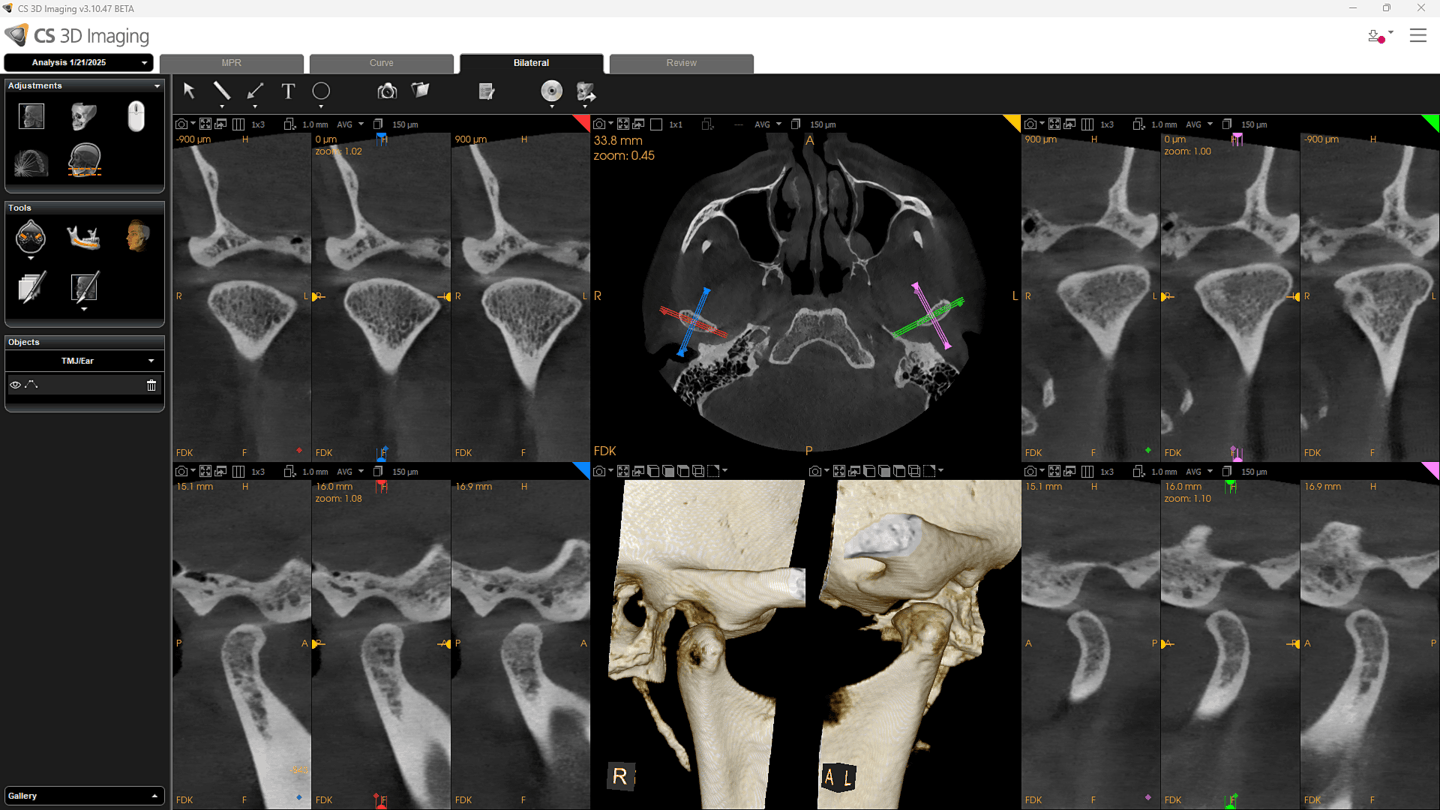

Fra 4×4 cm til et komplet 16×17 cm volumen. CS 9600 dækker endodonti, implantatplanlægning, oral kirurgi, ortodonti, ENT og maksilofacial kirurgi — alt fra én og samme platform.

Kliniske anvendelser

CS 9600 dækker et bredt spektrum af kliniske indikationer med dedikerede optagelsestilstande.